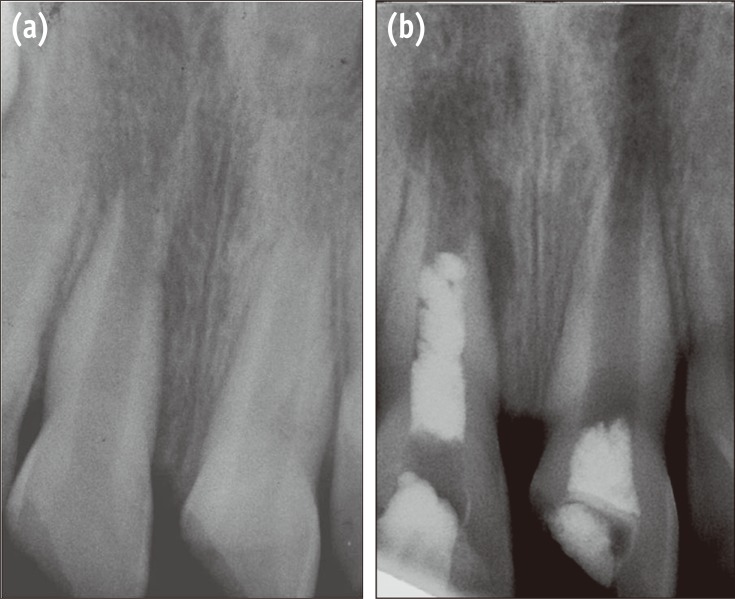

The patient was recalled 6, 12 and 18 months after the treatment. In clinical examination, the teeth were asymptomatic. In radiographic examinations, both teeth showed increased root lengths and apical closure. Root wall thickness had also increased, but the left central incisor showed greater improvements. The radiolucent lesion adjacent to the right central incisor had healed (Figures 2 and 3).